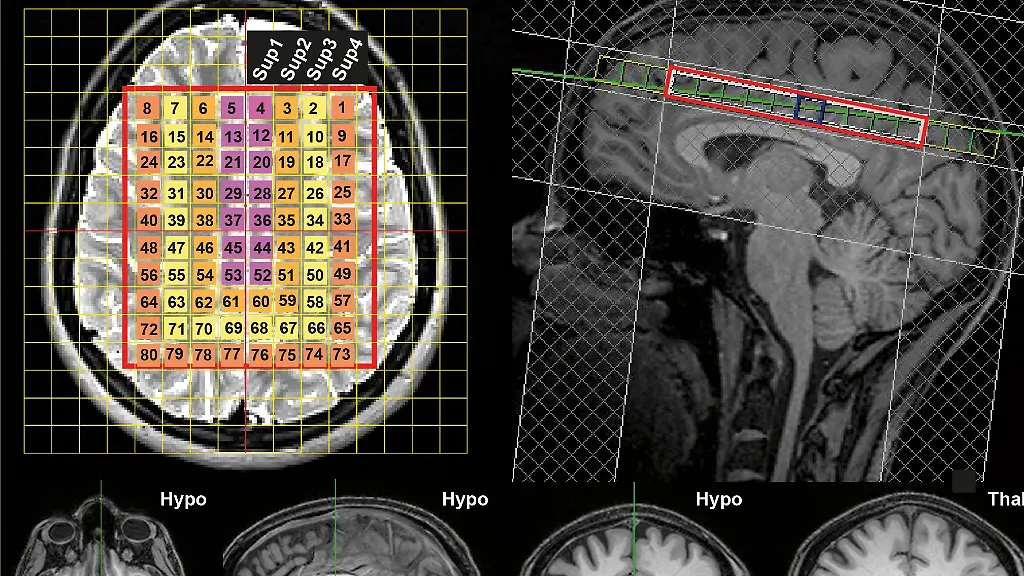

Basierend auf ihren Messungen erstellten die Forscher "HEATWAVE", eine 4D-Temperaturkarte des Gehirns: "Diese Karte stellt eine dringend benötigte Referenzquelle dar, mit der Patientendaten verglichen werden können. Sie könnte unser Verständnis von der Funktionsweise des Gehirns verändern", sagte Rzechorzek.